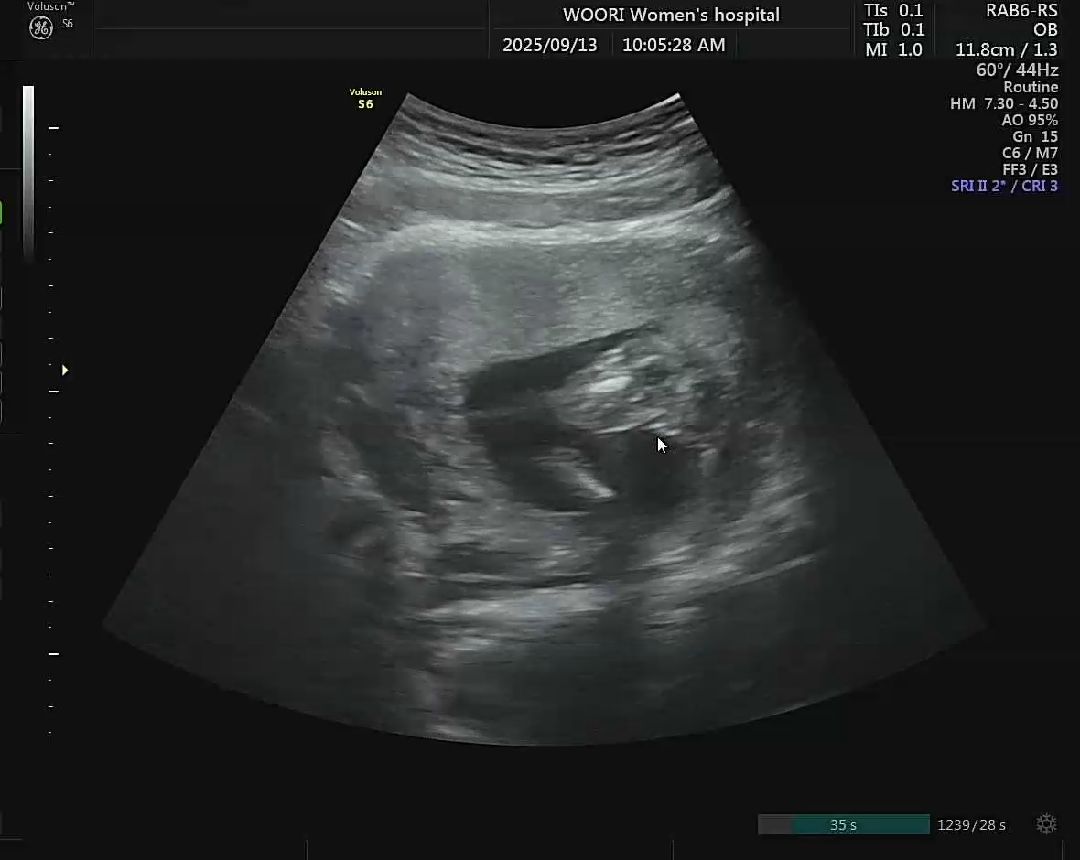

성별 질문& 양수량 늘리는법

딸이라고 받았는데 ... 양수가 살짝 부족해서 아가가 제대로 끼여있어 제대로 보이진 않더라구요ㅠㅠㅠㅠㅠ 맘님들이 보시기엔 어떠세용!? 저는 뭐 보이지가 않는데 가운데 저게 뭐가 있는 것 같기도 하고.. 혹시나 반전이 있을까 걱정되네용 고수맘님들 의견이 궁금합니다! 그리고 양수량 늘리는 법도 같이 알려주세요ㅠㅠㅠ